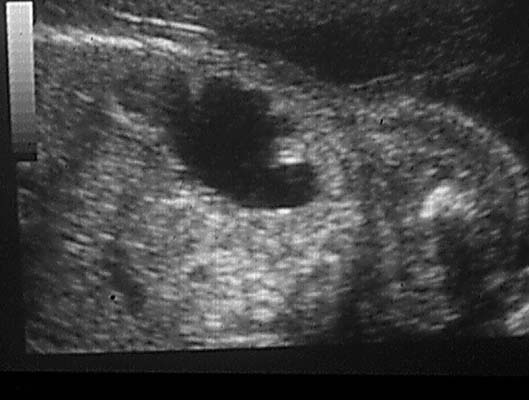

Dysplasie except